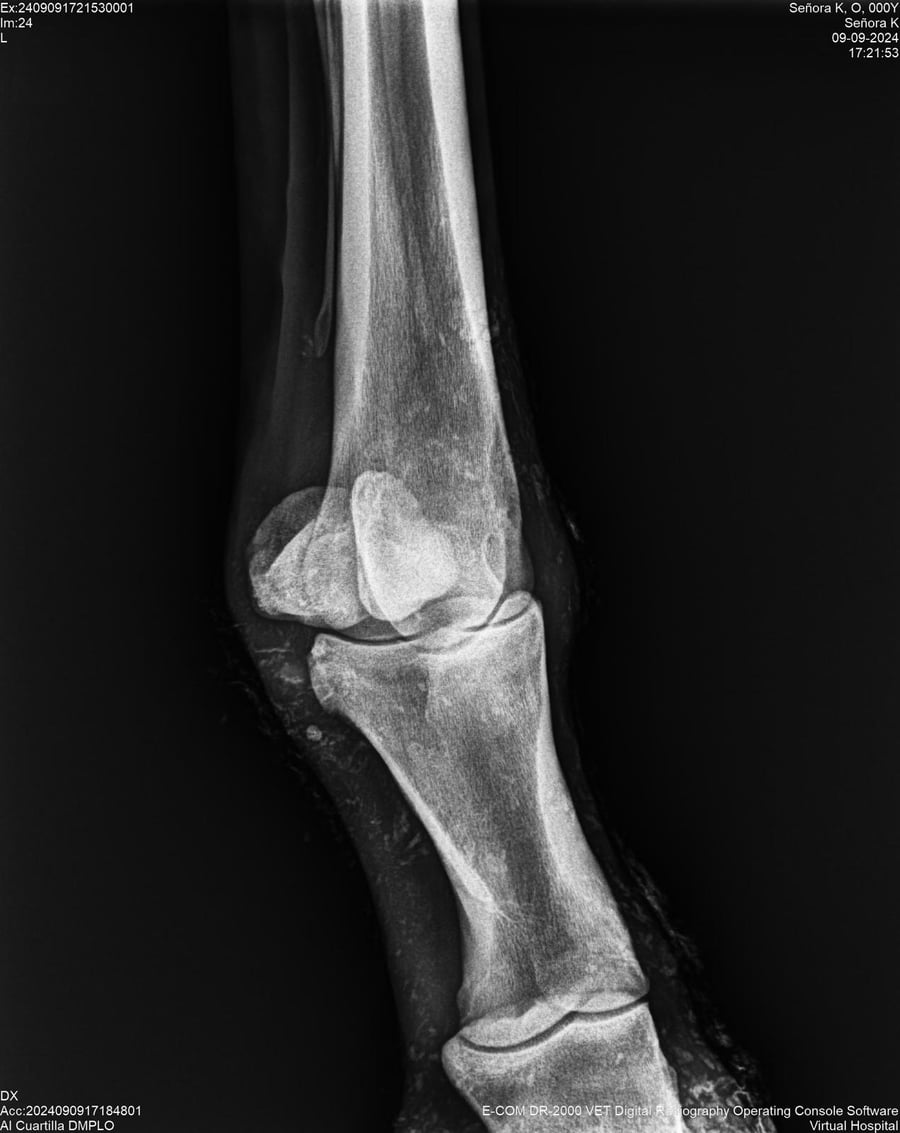

LOTE 44, SEÑORA K

Identificador: #291147-

Generacion 2022